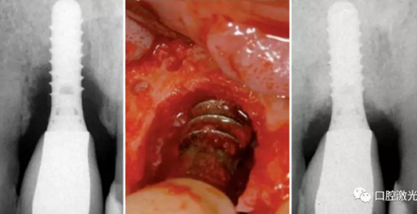

手術(shù)階段的目標(biāo)是為了能夠接觸到種植體的全部表面部位。從而可以完全去除結(jié)石,并且實施激光滅菌。手術(shù)介入治療是針對那些在初始階段治療效果不明顯的患者。通過內(nèi)切翻瓣,暴露整個種植體表面。小心去除種植體周圍的肉芽組織,如果在種植體表面看到結(jié)石附著,可以通過超聲或鉺激光進(jìn)行去除。隨后,對種植體表面的剩余物質(zhì)進(jìn)行激光照射滅菌。功率2W,連續(xù)模式照射10秒鐘,快速移動光纖尖,避免種植體表面溫度過高。

激光輔助種周炎手術(shù)治療前,中和手術(shù)后4年